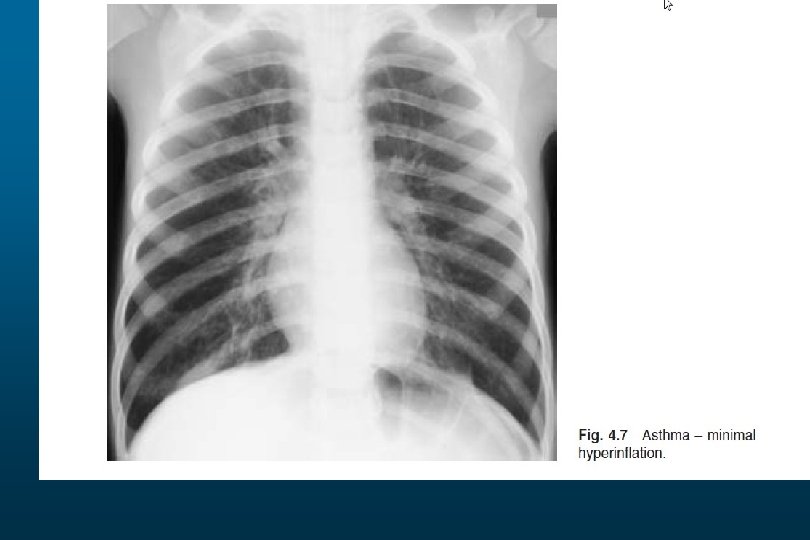

Pneumothorax